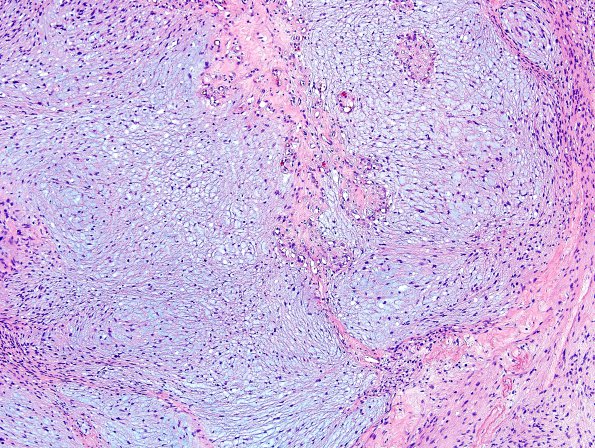

The neoplasm contains areas of myxoid change. The neoplastic cells have predominantly elongated ovoid nuclei and a 'stretched' appearance. In addition cells with large plump nuclei with irregular nuclear contours are also present, consistent with so-called ancient (degenerative) change. Mitoses are rare (<1/10HPF). The neoplasm contains focal areas with well-defined Verocay body formation.